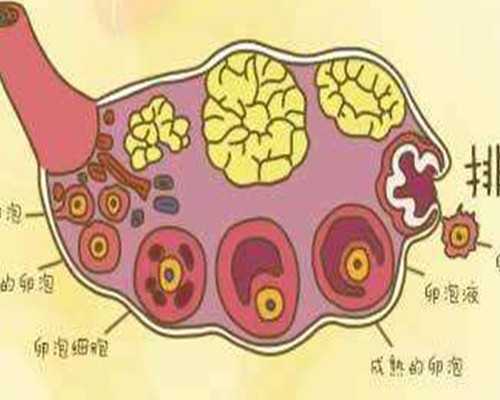

捐卵試管技術(shù):一代捐卵、二代捐卵

卵源等待時(shí)間:該院區(qū)卵源等待時(shí)間至少一年半起

2023煙臺(tái)市可開(kāi)展捐卵試管嬰兒技術(shù)的醫(yī)院共有2家,且均可開(kāi)展一代捐卵和二代捐卵試管技術(shù),不孕患者是可以將這2家醫(yī)院納入考慮范圍的。